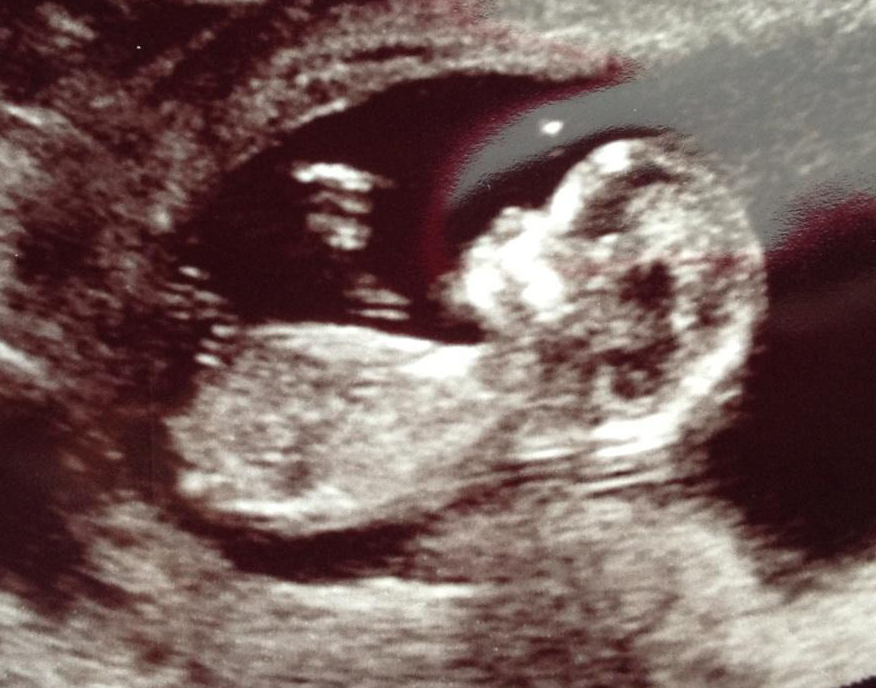

I'm interested in the nub and skull theory but can't quite figure my little one out. What is your best guess, girl or boy?Attachment 11732

Hmm... I dont know much about skull but I am not seeing a nub. How is that for not helpful at all? LOL!!

No nub in this pic

no nub and im totally 50/50 on this one x

No nub but fun guess of girl of off head

mamaG, no nub but skull looks girly!